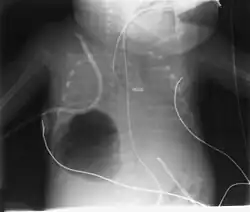

Large, right lower lobe pneumatocele is shown, compromising ventilation in a premature infant with RDS and superimposed RSV pneumonitis.

Diagnosis can be made using chest X-ray; the lesion shows up as a small, round area filled with air.[1] Computed tomography can give a more detailed understanding of the lesion.[1] Differential diagnoses – other conditions that could cause similar symptoms as pneumatocele include lung cancer, tuberculosis,[7] and a lung abscess[1] in the setting of hyper IgE syndrome (aka Job's syndrome), as a complication of COVID-19 pneumonitis,[8] or on its own, often caused by Staphylococcus aureus infection during cystic fibrosis.